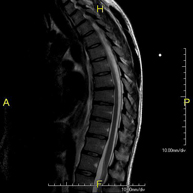

- Thoracic spine MRI

This non-invasive diagnostic procedure uses an electromagnetic field and radio waves (from a transmitter and receiver) to acquire high-definition anatomical images of the thoracic spine. It is a radiation-free procedure. Indicated for: trauma, degenerative problems, hernias, tumours.

- Cervical + thoracic spine MRI

This non-invasive diagnostic procedure uses an electromagnetic field and radio waves (from a transmitter and receiver) to acquire high-definition anatomical images of the cervical and thoracic spine. It is a radiation-free procedure. Indicated for: trauma, spinal degeneration, hernias.

- Thoracic + lumbar spine MRI

This non-invasive diagnostic procedure uses an electromagnetic field and radio waves (from a transmitter and receiver) to acquire high-definition anatomical images of the thoracic and lumbar spine. It is a radiation-free procedure. Indicated for: trauma, spinal degeneration, hernias.

A non-invasive diagnostic test that involves obtaining high-definition anatomical images of the thoracic and lumbar spine using an electromagnetic field and radio waves (with transmitter and receiver). It is a radiation-free procedure. Indicated for: trauma, spinal degeneration, hernias.